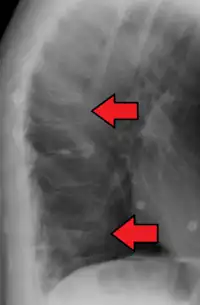

A compression fracture is a collapse of a vertebra. It may be due to trauma or due to a weakening of the vertebra (compare with burst fracture). This weakening is seen in patients with osteoporosis or osteogenesis imperfecta, lytic lesions from metastatic or primary tumors,[1] or infection.[2] In healthy patients, it is most often seen in individuals suffering extreme vertical shocks, such as ejecting from an ejection seat. Seen in lateral views in plain x-ray films, compression fractures of the spine characteristically appear as wedge deformities, with greater loss of height anteriorly than posteriorly and intact pedicles in the anteroposterior view.[3]

Compression fractures are usually diagnosed on spinal radiographs, where a wedge-shaped vertebra may be visible or there may be loss of height of the vertebra. In addition, bone density measurement may be performed to evaluate for osteoporosis. When a tumor is suspected as the underlying cause, or the fracture was caused by severe trauma, CT or MRI scans may be performed.

X-ray of the lumbar spine with a compression fracture of the third lumbar vertebra.